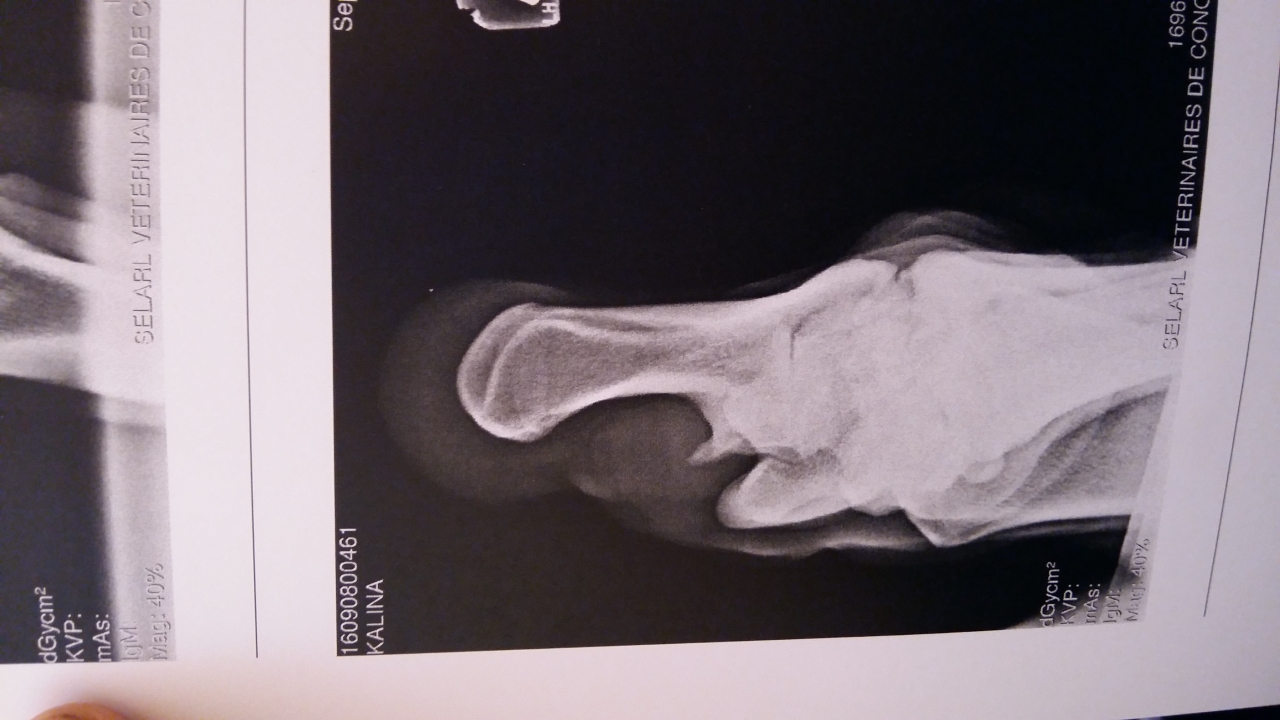

| Dire merci | Bonjour à tous ! J'ai amené ma jument de 18 ans à la clinique Lenormand pour des douleurs significatives sur l'antérieur droit et une tare molle sur le jarret gauche. pour la parenthèse cette tare molle est apparue en janvier suite à un mauvais coup. A l'époque le veto n'avait pas voulu faire de ponction et avait diagnostiqué un épanchement de synovie. Il n'y avait aucune douleur mais il y a quelques semaines j'ai noté douleur + augmentation de la taille de la tare Radios antérieurs Le veto s'est concentré sur les pieds uniquement parce que pour lui gros problème d'appui très visible à l'examen préliminaire. Je rappelle que ma jument est pieds nus. AG ![]() AD ![]() Radios postérieur gauche ![]() ![]() ![]() Bilan du véto Jument présentée pour une enflure en partie externe du jarret gauche. La distension implique la gaine tarsienne pas d'anomalie locomotrice, flexion négative. Boiterie AD sur cercle à main droite. La jument présente un aplomb AG avec des talons fuyants et un pied AD très légèrement encastelé. On note une diminution de l'appui sur l'AD. Radiographiquement on note une faible épaisseur de sole à G et à D. Présence de lésion d'éparvin marqué au niveau intarsien distal et tarso metarsien ainsi qu'une prolifération osseuse importante au niveau du sustentaculum tali. Echographiquement la prolifération osseuse vient en contact du tendon fléchisseur profond sans image de lésion du tendon visible. En conclusion distension de la gaine tarsienne G avec prolifération osseuse sur le sustentaculum tali à l'origine d'une tendinopathie chronique. Douleur aux pieds avec faible épaisseur de sole. Il est préférable de ferrer les antérieurs si la jument continue à avoir une activité. La gaine tarsienne a été infiltrée avec de la triacinolone. L'effet est probablement temporaire la distension devrait revenir plus ou moins rapidement en fonction de l'activité de la jument. Une intervention chirurgicale sous AG est possible [...] mais aujourd'hui elle ne présente aucune boiterie. |